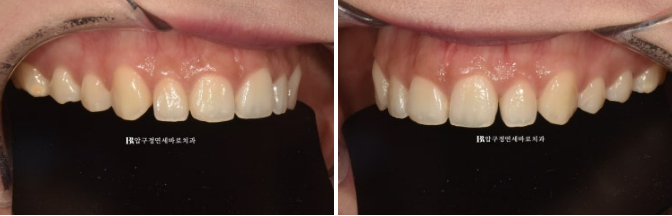

Sometimes, if this smile line is flat like the one above or curved in the opposite direction, the smile looks awkward.

As in the image below, the smile looks most beautiful when the smile line is parallel to the lower lip.

When making no-prep laminates, it is better to create a beautiful smile line by adjusting the lengths of the front teeth, lateral teeth, and canines.

Q. What does an unattractive smile line look like?

A. There are representative forms like these.

A line that is too straight and flat

A reverse smile line that curves upward

In such cases,

it can give a stiff or awkward impression when smiling.